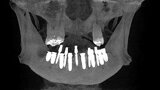

Implantacja z wykorzystaniem szablonu nawigacyjnego 3D